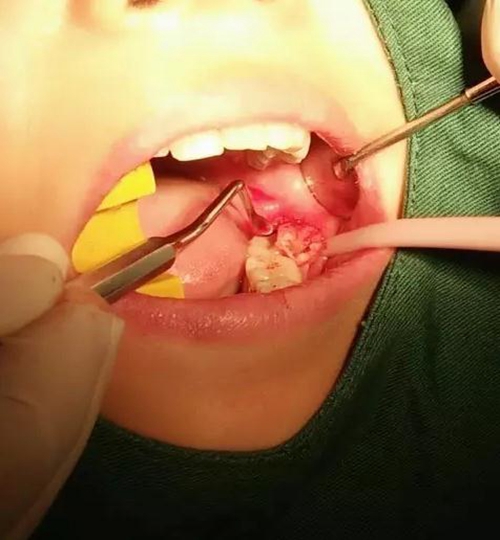

微創(chuàng)套裝,微創(chuàng)拔牙利器。

用到4號牙挺,避免敲擊拔牙根,稍有不慎,可能會出現(xiàn)牙根移位下頜神經(jīng)管。

挖匙取出

術(shù)中拍片發(fā)現(xiàn),還有剩余,繼續(xù)。。。。